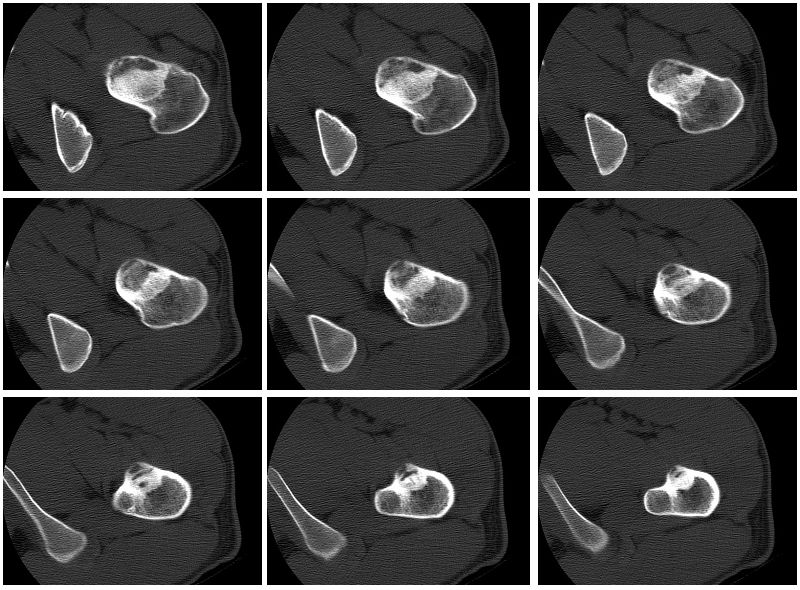

标题: CT27262:左股骨上段骨肿瘤 [打印本页]

标题: CT27262:左股骨上段骨肿瘤

男性,27岁,左髋部疼痛两三个月余,右侧髂骨因右侧股骨下端骨折,取骨植骨后改变

考虑左侧股骨颈及粗隆骨纤维异常增殖症。

磨玻璃样,男27岁考虑骨纤。